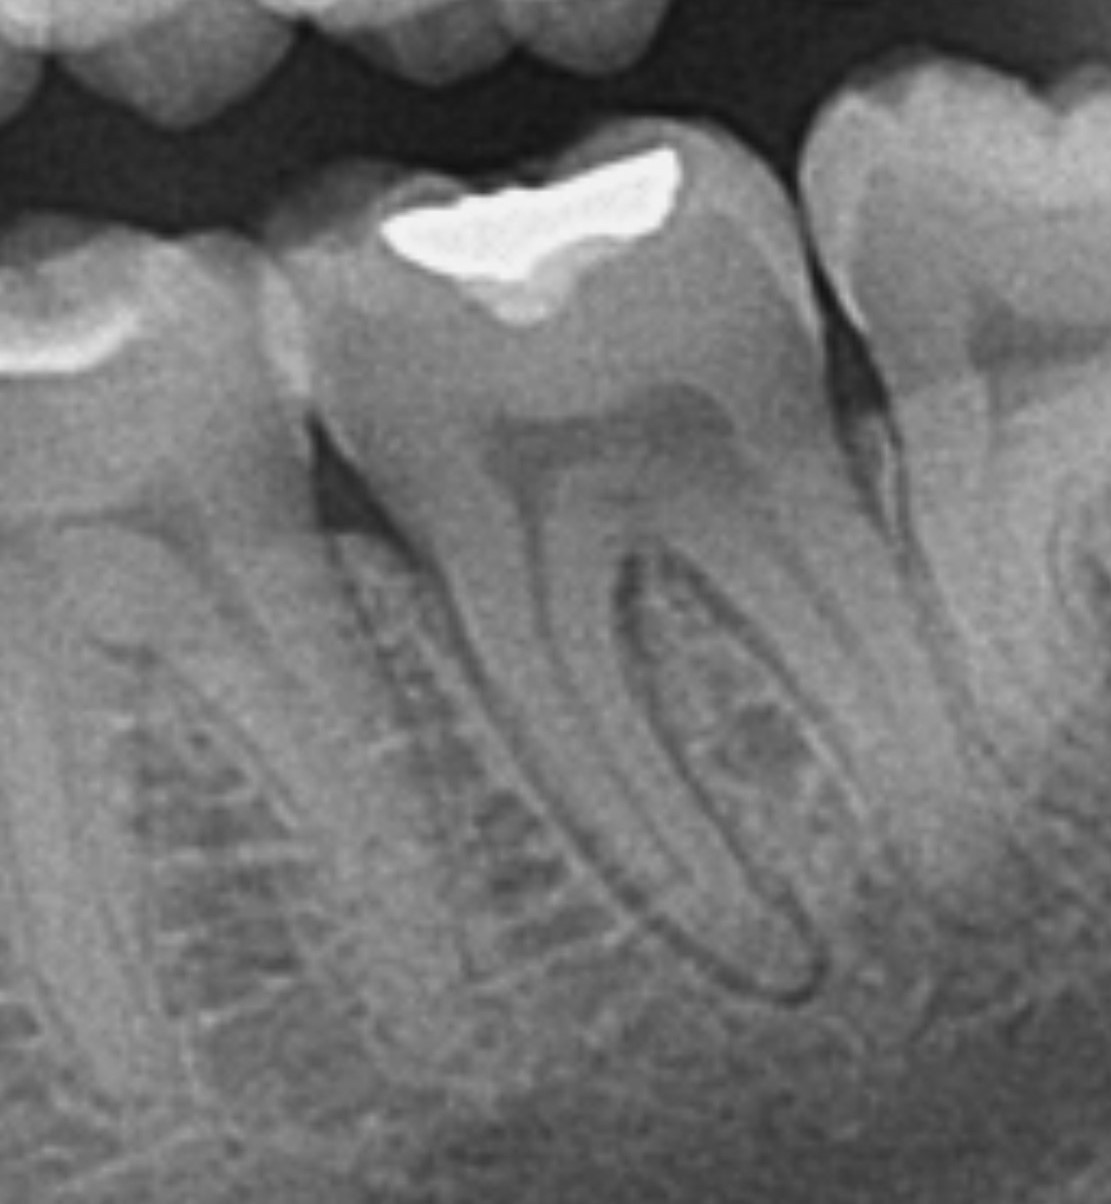

Regenerativni parodontološki zahvat kojim se kirurškim putem regenerirao infrakoštani defekt(parodontološki džep)